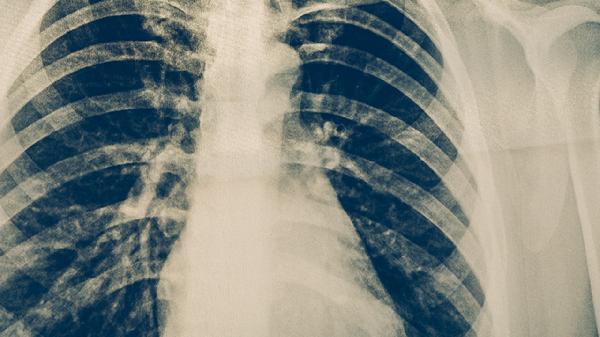

肺炎疫苗接种时间怎么安排 打一针便可预防肺炎吗

肺炎疫苗接种一般需要2-4针,具体时间安排需根据疫苗种类和接种对象年龄决定。肺炎疫苗不能完全预防所有肺炎,但能显著降低特定病原体引起的肺炎风险。